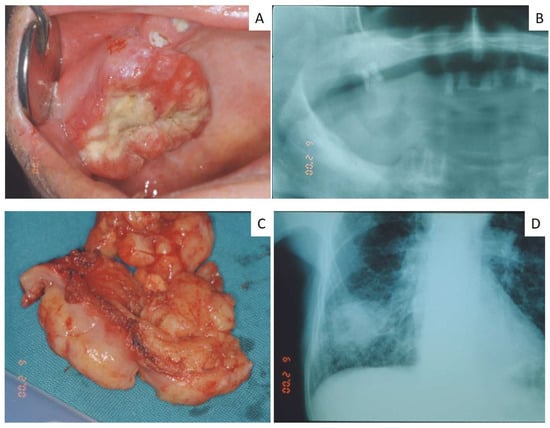

| Case | Age | Sex | Site/Sites | Primary Lung Tumor | Other Sites | First Sign of Disease |

|---|---|---|---|---|---|---|

| 1 | 43 | M | Submandibular lymph nodes | Non small cell carcinoma | n.a. | Yes |

| 2 | 52 | M | Submandibular lymph nodes | Non small cell carcinoma | n.a. | No |

| 3 | 65 | M | Gingiva | Non small cell carcinoma | n.a. | No |

| 4 | 82 | F | Gingiva | Squamous carcinoma | n.a. | No |

| 5 | 57 | M | Mandible | Non small cell carcinoma | n.a. | No |

| 6 | 68 | M | Submandibular lymph nodes | Non small cell carcinoma | n.a. | No |

| 7 | 62 | M | Gingiva | Non small cell carcinoma | n.a. | No |

| 8 | 67 | F | Submandibular lymph nodes | Non small cell carcinoma | n.a. | No |

| 9 | 50 | M | Submandibular lymph nodes | Squamous carcinoma | n.a. | Yes |

| 10 | 79 | M | Gingiva/palate | Non small cell carcinoma | n.a. | Yes |

| 11 | 65 | M | Gingiva/tongue | Squamous carcinoma | n.a. | No |

| 12 | 57 | M | Submandibular lymph nodes | Small cell carcinoma | n.a. | No |

| 13 | 65 | M | Submandibular lymph nodes | Squamous carcinoma | n.a. | No |

| 14 | 80 | M | Mandible | Squamous carcinoma | Vertebra | No |

| 15 | 67 | M | Maxillary gingiva | Squamous carcinoma | Vertebra | No |

| 16 | 65 | M | Parotid gland | Small cell carcinoma | n.a. | Yes |

| 17 | 70 | F | Maxillary gingiva Around dental implant | Small cell carcinoma | n.a. | Yes |

| 18 | 62 | M | Maxilla gingiva Around dental implant | Adenocarcinoma | n.a. | Yes |

| 19 | 65 | F | Tongue | Small cell carcinoma | n.a. | Yes |

| 20 | 72 | F | Maxillary gingiva | Adenocarcinoma | n.a. | Yes |

| 21 | 66 | M | Tongue | Small cell carcinoma | Brain | No |